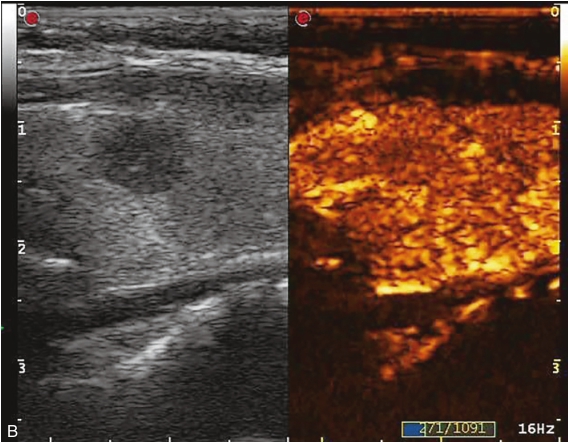

甲状腺右叶中部可见一个肿块,大小约为2.6cm×1.8cm×1.8cm,形状尚规则,边界尚清楚,内部为低回声,分布不均匀,后方回声无变化,CDFI显示肿块内可见丰富的血流信号,见图1-9-1。

图1-9-1 甲状腺髓样癌常规超声图像

A.甲状腺右叶低回声结节纵切面灰阶超声图像;B.甲状腺右叶低回声结节横切面灰阶超声图像;C.CDFI图像

注射造影剂后,10s病灶早于周围甲状腺组织开始增强,呈不均匀高增强,13s达峰值,19s开始减退,至增强晚期病灶减退呈不均匀稍低增强。见图1-9-2、ER1-9-1。

甲状腺髓样癌常见超声造影表现为低增强、不均匀低增强及向心性低增强。但若病灶内血管分化较多,也可能出现高增强表现。

图1-9-2 甲状腺髓样癌造影图像

A.造影后10s;B.造影后13s;C.造影后19s;D.增强晚期